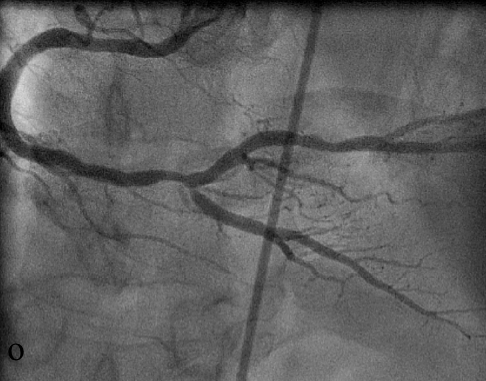

При коронарографии ПКА выявлен выраженный стеноз дистального сегмента ПКА с переходом на устье ЗМЖВ (о). В дистальную треть ПКА с переходом на устье ЗМЖВ был имплантирован стент XienceV, сужение устранено, достигнут хороший ангиографический результат (п).